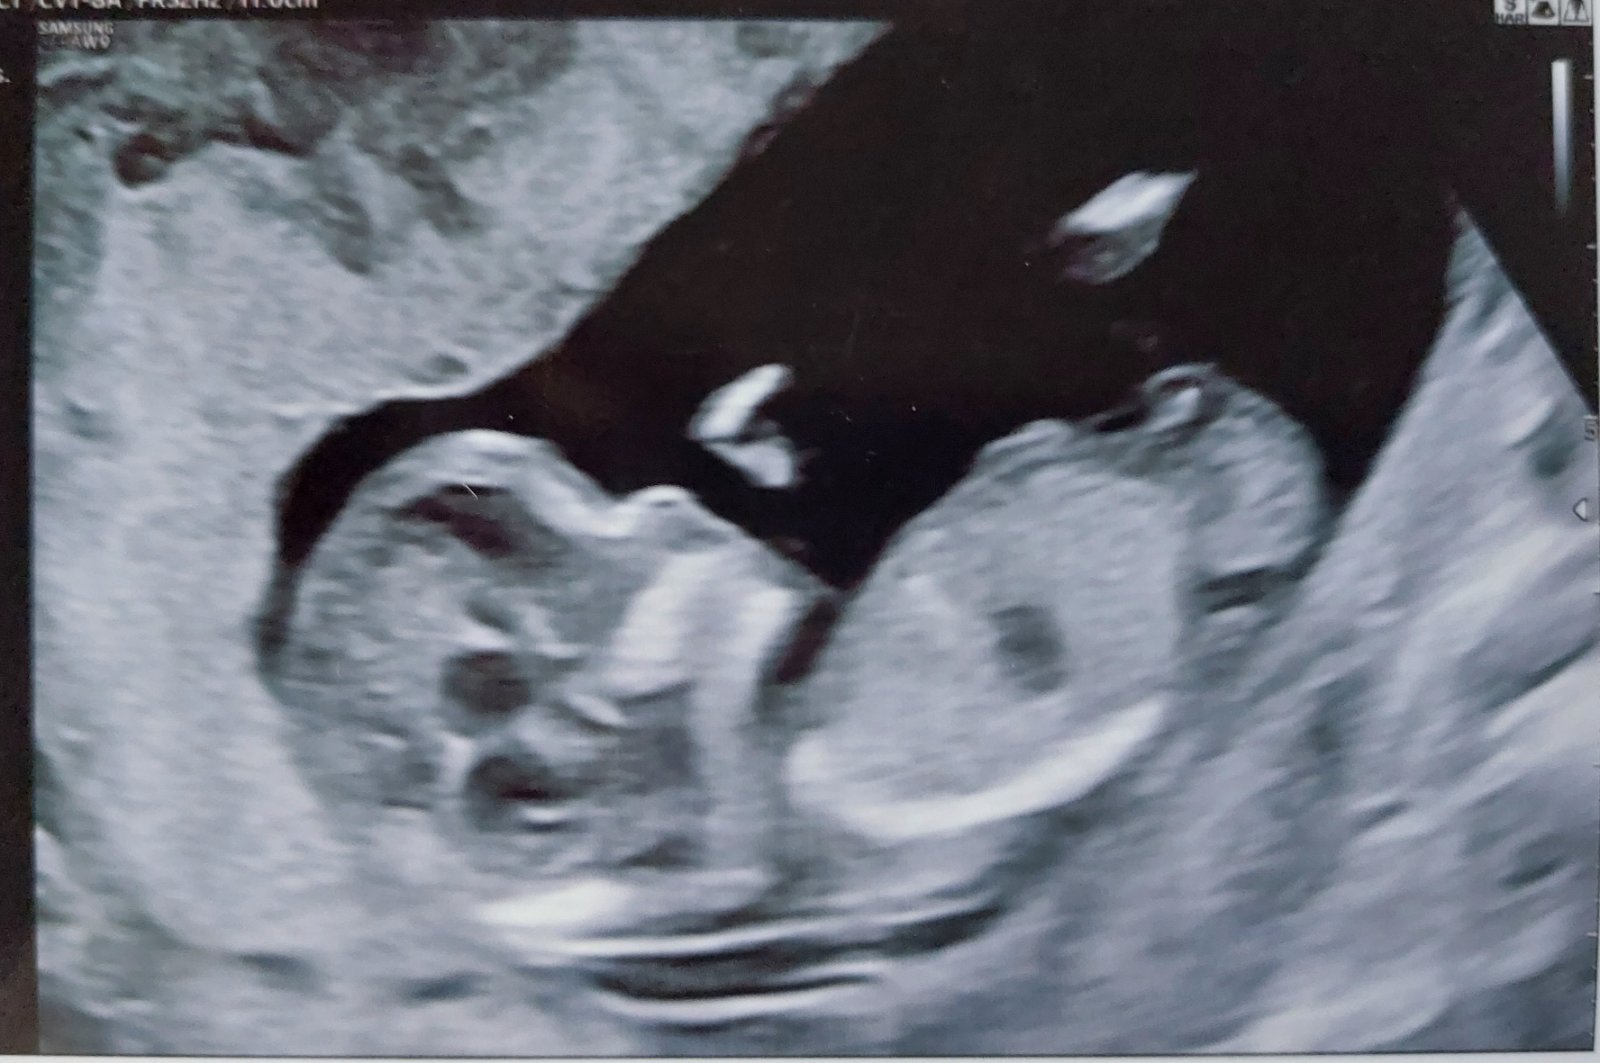

Poznáte pohlaví dítěte z ultrazvuku ve 13. týdnu?

Minulé těhotenství mi to takto brzy řekli s jistotou a trefili se. Nyní jsem se ani nezeptala, protože jsem byla úplně na nervy, jak dopadne screening a teď jen přemýšlím, jestli by to z fotky šlo poznat

Ano, dá se to poznat už kolem toho 12.týdne, ale bohužel u tvé fotky nevidím hrbolek 🙂 snad se příště ukáže líp